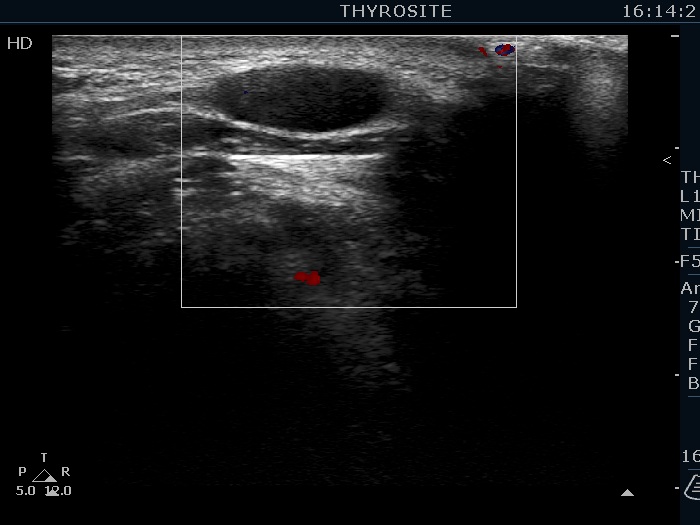

Ultrasonography. The thyroid was echonormal. There were several hypoechoic nodules in the left lobe. The middle one had back wall cystic figures. There were 3 or four discrete, deeply hypoechoic lesions above and lateral to the left lobe in the neck. One of them presented with a hilum-like figure while the others lacked hilum.

Aspiration cytology of the lesion in the middle part of the left lobe resulted in benign lesion. One of the masses in the neck was also aspirated and a heterogeneous lymphoid cell population was gained. Wash-out thyroglobulin resulted in 13 ng/mL, while serum thyroglobulin was 19.4 ng/mL.

The lymph nodes had a non-typical presentation. They lacked a regular hilum.